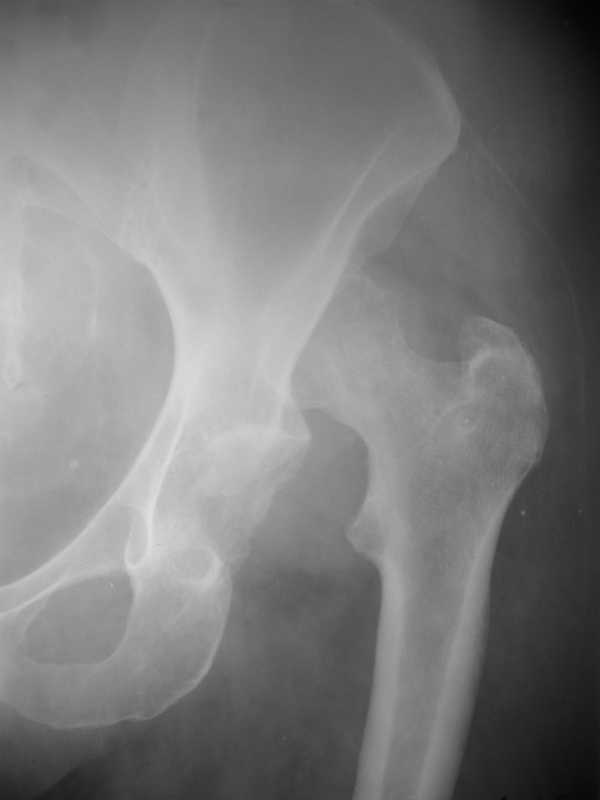

Застарелый вывих бедра

Уважаемые коллеги! Обратилась больная К. 57 л. Травма 1,5 года назад -упала на улице, обращалась в травмпункт.

Была отпущена домой с диагнозом ушиб левого тазобедренного сустава. Ходила с костылями. В данный момент жалобы на умеренные боли в левой нижней конечности, укорочение 6 см. Имеется контрактура левого тазобедренного сустава. Предлагается обсудить тактику лечения: начать с наложения дистракционного аппарата с постепенным низведением головки бедра и последующим эндопротезированием тазобедренного сустава.

головка бедра давно умерла, поэтому кроме эндопротезирования ей ничего не грозит, за исключением мучений низведения бедра в АВФ. другого пути здесь нет! одномоментно вытянуть эту ногу, да же если удастся, то повиснет стопа. надо Обьяснить пациентке что ее ждет. и вообще, если она с "ушибом" столько ходила, то может и дальше с ортопедической стелькой пойдет????

смысл аппарата? некроз уже есть.

Коллеги, как-то сказать с уверенностью что головке - хана! (некроз), по этим снимкам - ....сомнительно как-то, хотя....хотя, "все может быть".

низведение бедра в АВФ с последующим эндопротезированием, состояние головки бедра не имеет особого значения, скорее всего рассосется при любом виде операции, да и без нее.